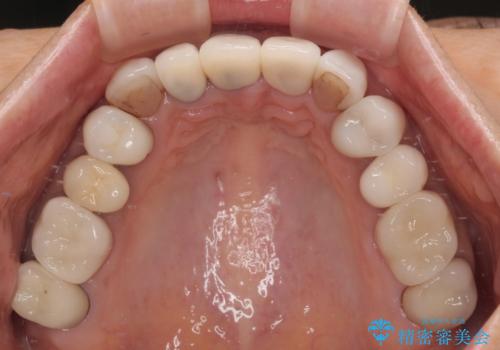

- 前歯のセラミックが欠けたり色調が不揃いであったりすることを気にして来院された患者様です。

20年以上前から、むし歯になったり詰め物が欠けたりする度に部分的に処置を行ってきたそうですが、この際統一感のある前歯にしたいとのことで、上顎前歯9本をオールセラミッククラウンによる補綴治療を行うこととしました。